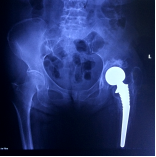

術(shù)后X線片